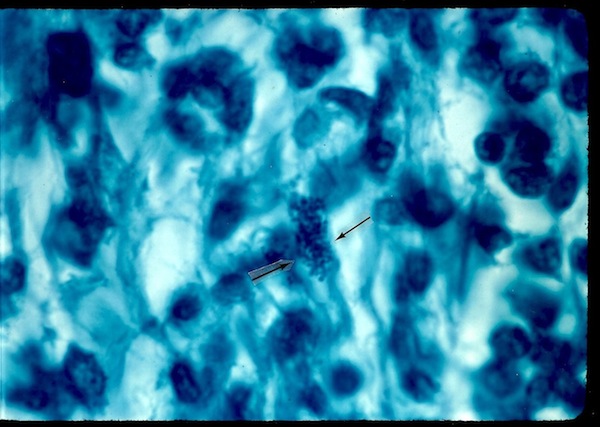

Figure

2. Breast cancer showing a clump of intracellular coccoid forms (long

arrows)

and scattered extracellular coccoid forms. Acid-fast stain, x1000, in

oil.